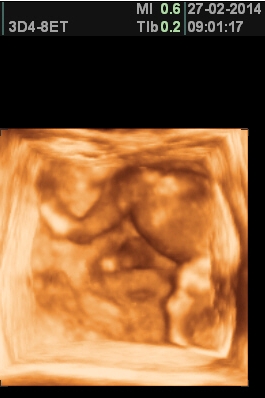

[550892] Káťo fajné fotečky, jaká pohodička...;-)